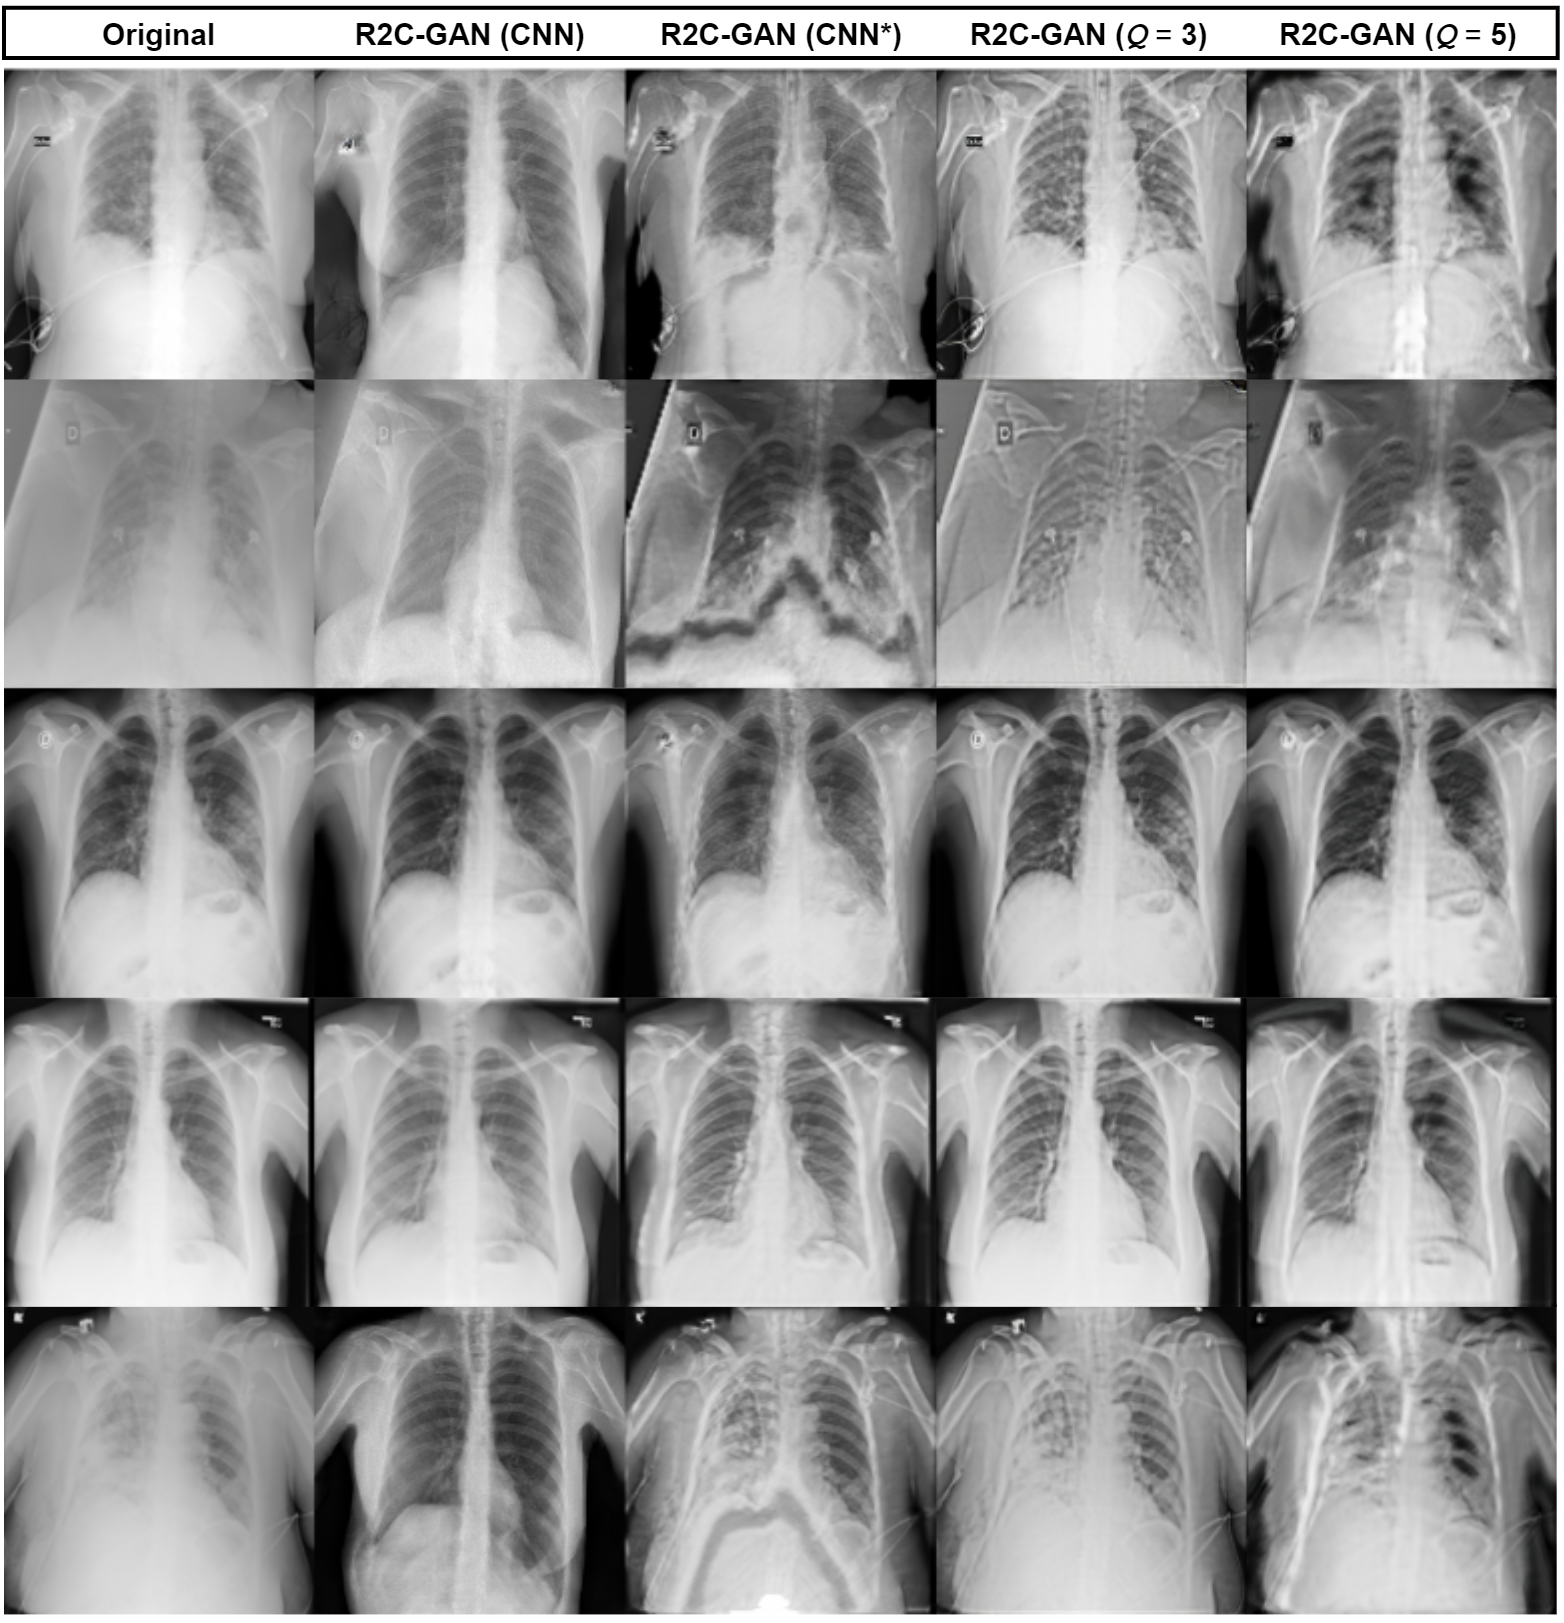

Refer to caption

Figure 6: Original samples with the corresponding restorations of different R2C-GAN models are shown in each column.

The qualitative evaluation is performed over 200020002000 randomly selected samples from the test set. The original and its corresponding four different restored X-ray images obtained from R2C-GAN (CNN), R2C-GAN (CNN*), R2C-GAN (Q=3𝑄3Q=3), and R2C-GAN (Q=5𝑄5Q=5) models are used for the evaluation. Accordingly, we split the samples between four MDs who are experts in the field of COVID-19 diagnosis from chest X-images and they are asked which X-ray image (the original or four different restored versions) they would prefer for the diagnosis considering the provided disease labels. In Fig. 6, one row represents one query that is presented to the MD for voting. Note that for a given row, the selection is performed blindly so that the MDs do not have the information about the column labels. Then, the selection ratio is computed for each restored version including the original images as presented in Table III. It is observed that using operational layers in R2C-GANs with Q=3𝑄3Q=3 achieves the highest overall restoration performance. Due to the subjective evaluation, several MDs have preferred the original images for the diagnosis, while MD III and IV have voted more for the restored images by R2C-GAN (Q=3𝑄3Q=3) model than for the original images with selection ratios larger than 55%percent5555\%. We have observed that during inference, iterative restoration of the images improves the performance of the compact R2C-GAN models, whereas the deep R2C-GAN model introduces more blur in the iterative restoration. Therefore, the presented restored images to the MDs are obtained by consequently applying the generators three times, i.e., for a given image sample 𝐲𝐲\mathbf{y}, the generator G𝐺G is applied three times: GGG(𝐲)𝐺𝐺𝐺𝐲G\circ G\circ G(\mathbf{y}) while the generator of deep R2C-GAN (CNN) is applied only once. In Fig. 6, it can be observed that satisfactory restoration results are obtained using R2C-GAN (CNN) and R2C-GAN (Q=3𝑄3Q=3). While the R2C-GAN (CNN*) model produces certain artifacts, R2C-GANs (Q=3𝑄3Q=3) restores without any artifacts and the restored images are shaper with significantly more details. Considering the fifth row in Fig. 6, R2C-GAN (CNN) removes the disease information on lung areas and makes the region more blackish. Finally, it is shown that when the input image has already a high overall quality as in the third row, the proposed approach tends to keep the high quality after the transformation applied. We have also observed that the proposed restoration approach occasionally removes a part of a text or sign on the X-rays. It is important to note that the restoration aims to present an alternative but mostly superior visualization of the original X-rays for better diagnostics and analysis. If such an occasional restoration artifact is encountered, it can, therefore, be easily compensated by the MDs by analyzing the original X-ray.